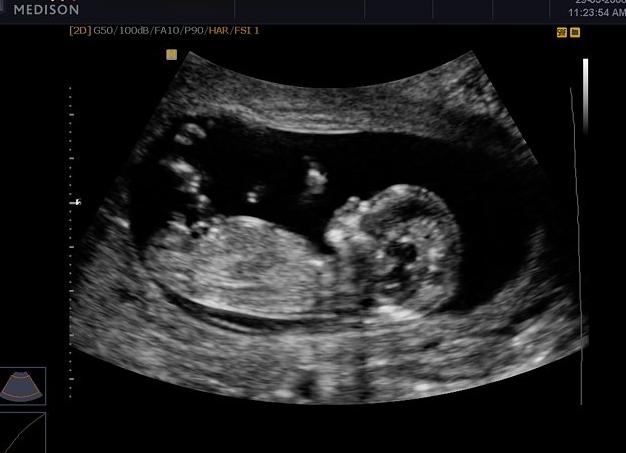

УЗИ — если оно не было выполнено в 10 или 11 недель, необходимо пройти на 12 неделе беременности. В ходе исследования врач выяснит, соответствует ли развитие плода сроку, оценит состояние внутренних органов малыша и определит место прикрепления плаценты. Если на раннем сроке вы еще не делали УЗИ, то 12 недель — самый подходящий срок для того, чтобы его провести. Вообще, первое обязательное исследование можно сделать и в 11, и в 13, и в 14 недель, но большинство женщин, все же, направляются на него именно на 12-недельном сроке. УЗИ, выполненное в 12 недель, позволяет узнать информацию, которая недоступна при исследовании на других сроках (ранее 11 и позже 14 недель). Матка женщины уже увеличена более, чем в 2 раза по сравнению с исходным размером и сейчас она достаточно большая для того, чтобы УЗИ можно было сделать без использования вагинального датчика, который так не нравится многим женщинам. Обычно исследование выполняют классическим способом, через кожу живота. Главное, что интересует специалиста при проведении УЗИ — это, конечно, плод. Его размер в этот период сопоставим с длиной женского мизинца, частота сердечных сокращений составляет до 160 ударов в минуту, желточный мешок уже не визуализируется, формирующаяся плацента может быть прикреплена к любой из стенок или дну матки. Не переживайте, если на первом ультразвуковом исследовании (УЗИ) выявится низкое предлежание плаценты, поскольку в 90% случаев она сдвигается выше к 28 неделе беременности. При УЗИ плода в 12 недель беременности измеряется кроме длины эмбриона (копчико-теменной размер — КТР), размер головки плода (окружность головы, бипариетальный размер, лобно-затылочный размер). Обязательной при УЗИ плода в 12 недель беременности является оценка структур головного мозга плода, симметричность полушарий. В норме головной мозг плода на УЗИ имеет вид бабочки. Измеряются длинные кости плода (плечевые, локтевые, лучевые, бедренные, большеберцовые, малоберцовые), производится оценка симметричности конечностей, их двигательной активности. При УЗИ плода в 12 недель беременности измеряется поперечный размер живота плода, окружность живота, отмечается наличие желудка, сердца в типичных местах. При проведении УЗИ плода в 12 недель беременности можно заподозрить наличие пороков сердца при достаточной разрешающей способности ультразвукового сканера и должном опыте и образовании оператора УЗИ. Есть опубликованные данные диагностики транспозиции магистральных сосудов, общего атрио-вентрикулярного канала, эктопии сердца и т.д., зарегистрированные при проведении УЗИ плода в 12 недель беременности. Врач не только видит сами очертания ребенка, но и рассматривает его органы, доступные визуализации: кости свода черепа, желудок, передняя брюшная стенка, мочевой пузырь, нос, позвоночник, кости конечностей. Также оценивается размер носовых костей и воротниковой зоны. Изменения этих областей могут говорить о том, что у ребенка возможно наличие хромосомных аномалий. На 12 неделе толщина воротникового пространства составляет 1,5–1,8 мм, размер носовых костей — 1,6–1,9мм. Копчиково-теменной размер на сроке 12 недель составляет 53 мм — показатель нормы. При незначительном отклонении причины переживать нет, так как возможны небольшие нормальные колебания, которые в среднем составят от 42 до 59 мм. (КТР) плода (ребенка), является наиболее точным параметром для определения срока гестации — то есть срока ваше беременности Опытные специалисты, работающие на хороших аппаратах, во время исследования УЗИ в 12 недель иногда могут сделать предположение о поле ребенка, однако это предположение далеко не всегда точное, поэтому полагаться на него не стоит. Размер ребенка от темени до копчика составляет порядка 5–6 см, что уже весьма немало, в сравнении с тем, что было ровно половину срока назад, когда величина эмбриона была всего 5–6 мм. В этот период ребенок активно растет, при исследовании его можно увидеть, как вполне симпатичного человечка с короткими ручками и ножками, что вызывает у будущих мам умиление, а у особо чувствительных из них — даже слезы. Ребенок активно двигается, машет ручками, дрыгает ножками, зевает. Главная задача УЗИ — определить пороки развития. В случае подозрения на аномалии пациентку посылают к генетику, который определяет вероятность появления ребенка с проблемами. Если эта вероятность высока, женщине предлагается нелегкое решение — прервать беременность или оставить ребенка. Помимо пороков, УЗИ определяет такие нарушения, как признаки недоразвития малыша, низкое прикрепление плаценты, гипертонус матки и многое другое. Все выявленные расстройства обязательно регистрируются в заключении к процедуре. Затем гинеколог изучает протокол исследования и на основании своих выводов предлагает будущей маме тот или иной вариант лечения. Результаты УЗИ помогают выявить неблагоприятные прогностические признаки в ранние сроки беременности до 12 недель:

У малыша начинают появляться ноготки на пальчиках и первые волоски на коже. На УЗИ прекрасно видно как малыш переворачивается и кувыркается, правда пока эти движения произвольны. Также у малыша уже сформировались мочки ушей, развивается костная система и начинает функционировать кишечник. На 12 неделе беременности у малыша начинает работать щитовидная железа, которая регулирует обмен веществ и рост.

Плановое ультразвуковое исследование (УЗИ) приходится на 12-14 неделю беременности. Часто в просторечии его называют генетическое УЗИ. В это время эмбрион уже приобретает вид сформированного человека.

Во время исследования можно предварительно оценить строение головы, туловища, конечностей, внутренних органов. Видно и слышно работу сердца, хорошо видны движения.

Генетическое исследование, кроме стандартных измерений, выполняемых при каждом плановом УЗИ, основывается также на измерении так называемого продуктивного параметра, оценивающего отек подкожной клетчатки в области воротникового пространства плода.

Это расстояние между подкожной тканью и кожей на высоте шеи плода. Увеличенное значение предполагает наличие у плода генетических дефектов, таких как синдром Дауна, синдром Эдвардса или другие отклонения.

Генетическое УЗИ выполняется именно в 12-14 недель, потому что алгоритм считающий риск развития генетических заболеваний, разработан для эмбрионов, размером 45-84 мм, то есть, находящихся как раз на этих неделях беременности.

Будущим родителям после прохождения УЗИ, как правило, вручают первое фото малыша, с которого и начнётся история детского фотоальбома. Ребенок уже имеет прекрасно развитое лицо, линию носа и подбородка. На этом этапе родители впервые начинают спорить о том, на кого больше похож малыш.